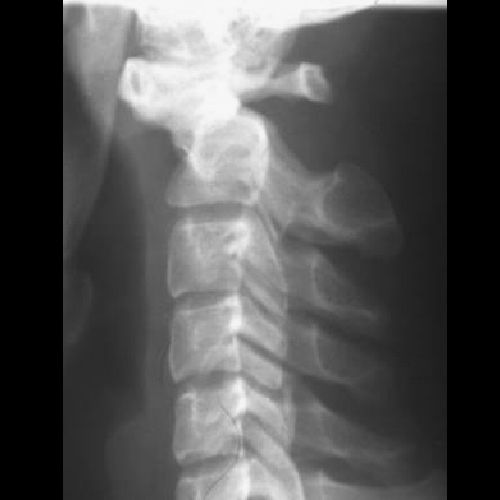

Для задней фиксации верхнешейного отдела позвоночника при его тяжелых повреждениях и заболеваниях.

- повреждения

- деформации (приобретенные и врожденные)

- опухоли